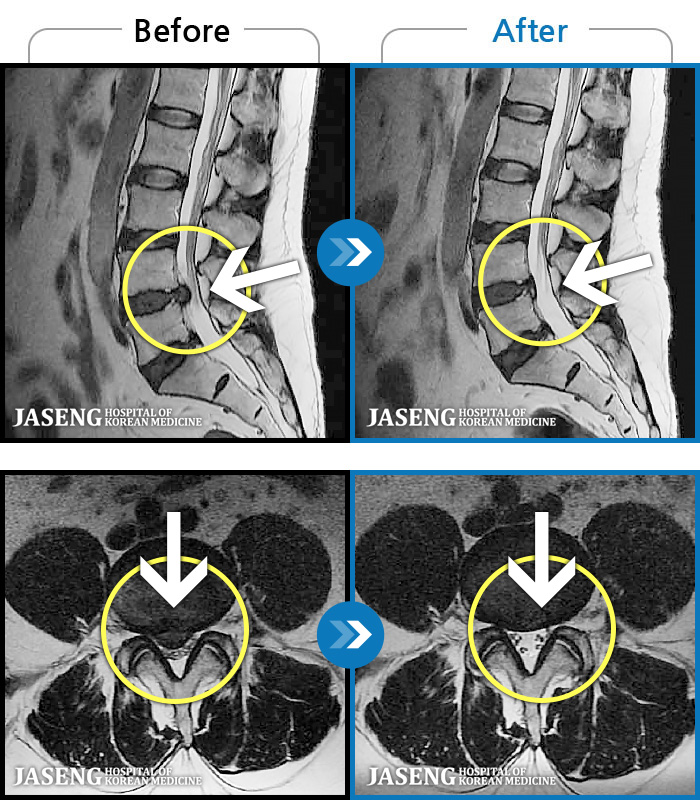

MRI ġ

119 MRI ũ ʸ Ȯϼ.

[Կñ:23.08.01~23.11.18]

[_㸮ũ] 㸮 ٸ ؼ ɰų

No.116

ȸ 730

2023.12.08